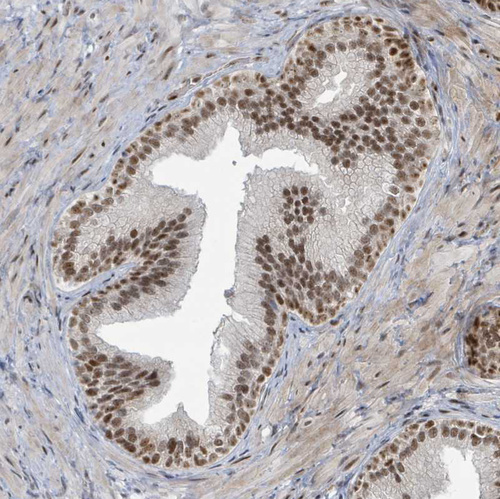

Immunohistochemical staining of human colorectal cancer shows strong nuclear positivity in tumor cells.